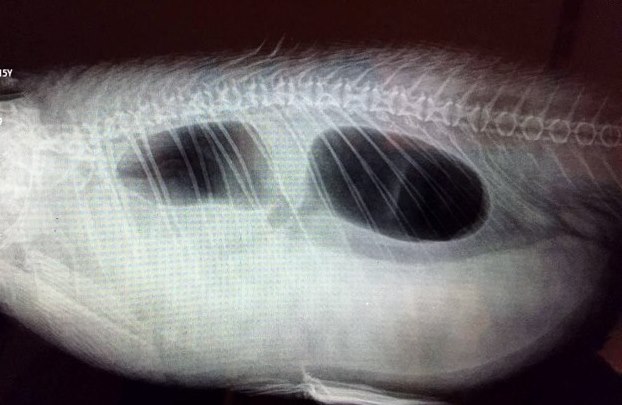

Sie hat den Chagoi geröntgt , Ultraschall und Abstrich gemacht, gewogen und ihm eine Cortison Volon A Spritze gegeben und eine Vitaminspritze.

Am Tag danach hat sie das Röntgenbild an einen anderen Koiarzt geschickt der ihr geraten hat die kleinere Schwimmblase zu punktieren.